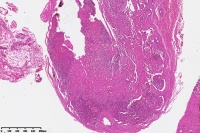

网状血管内皮瘤?血管瘤机化再通?血管肉瘤?

性别

女

年龄

41岁

右小环指指璞部包块

肉芽肿性毛细血管瘤。

考虑:血栓

机化再通

混合型血管瘤。